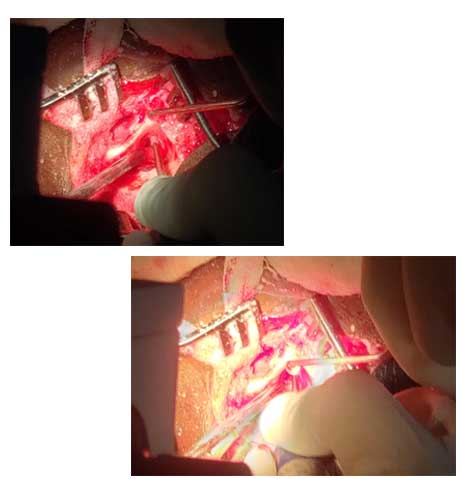

42/M Patient came with H/o self inflicted, cut throat Diagnosed -Self inflicted cut injury /zone-1 and 2 neck injury . Presented with severe bleeding, hypovolumic shock .Airway secured and fluids started . Pt was shifted to emergency OT and resuscitation started and stabilized by our anesthesia team. Patient underwent Emergency exploration of neck and bleeding IJV was ligated and ryles tube inserted .There were two penetrating wounds in neck , one in zone 1 which was exposed and Tracheostomy done. In zone 2, there was complete transection of thyroid cartilage and epiglottis, completely separated and tear went upto pyriform mucosa. Cartilage repair and mucosa repair done . It is first of its kind , cut throat injury with vessel bleed and pt revived in almost arrested stage and successfully surgical repair done .